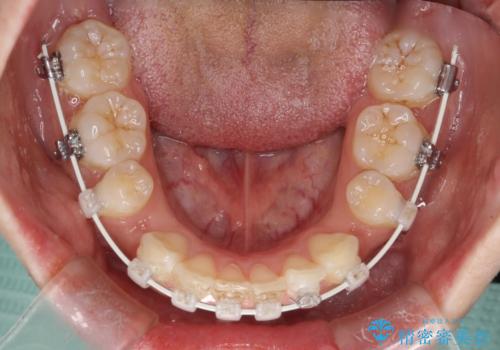

- 矯正装置

- 審美装置

- 横から見たときの口元が出てるの気になるとのことで来院されました。

口元の突出感と口唇の閉じずらさが確認されました。

上下左右の歯を1本ずつ、合計4本抜歯しして前歯を後方に下げて、口元の突出感を改善する計画としました。